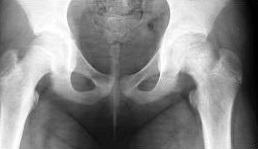

Dziecko w wieku 5 lat i 9 miesięcy zgłosiło się do ortopedy z powodu dolegliwości bólowych lewego stawu kolanowego i okresowych dolegliwości bólowych lewego stawu biodrowego. W badaniu klinicznym stwierdzono niewielkie ograniczenie ruchów odwodzenia w stawie biodrowym i rotacji do wewnątrz. Podczas chodzenia dziecko wyraźnie utyka na kończynę dolną lewą. Objaw Trendelenburga jest dodatni. Wykonany w dniu badania radiogram stawów biodrowych zamieszczony jest poniżej. Obraz kliniczny i radiologiczny przemawia za: